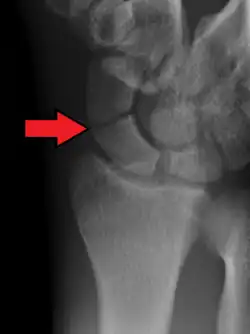

An X-ray showing a fracture through the waist of the scaphoid

Fracture of the tubercle of the scaphoid bone of the wrist